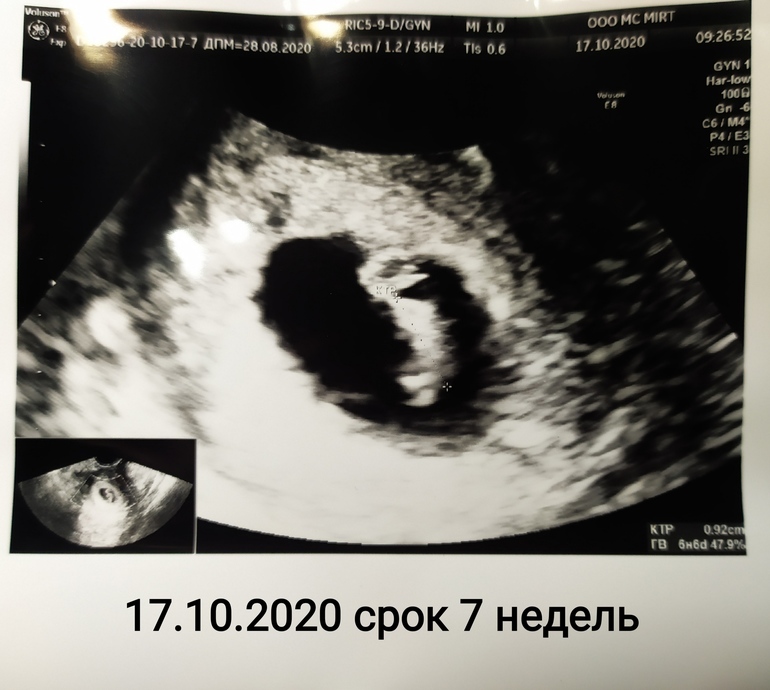

УЗИ 7 недель результаты

Была 17.10 на УЗИ, по М написали 7+1 (по факту думаю 6+6 или 7, так как О отслеживала по БТ, была на 16 дц, что для меня даже рано)

Узист сказала, что соответствуем сроку

КТР 9 мм, СВД ПЯ 20 мм, чсс 136 уд/мин